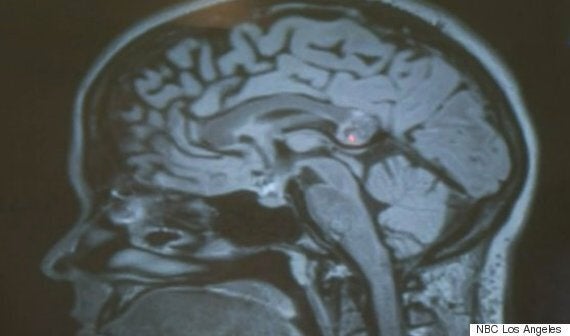

A red light shows the growth in Yamini Karanam's brain, initially believed to be a tumour